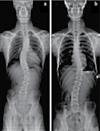

손, 발, 다리의 통증, 저림, 근육약화감, 감각상실 (편)두통 / 불면증 / 어지러움 / 턱관절 장애(TMJ) 척추측만증(Scoliosis) / 척추협착증 / 허리수술 후유증 허리통증 / 허리 디스크 / 관절염 / 좌골신경통 / 고관절, 발목, 손목 통증 ▪ ▪ ▪ ▪ ▪ ▪ ▪ ▪ ▪ 최첨단 목/허리 디스트 치료기기 최신형 디지털 X-ray 시설 Therapeutic Massage ▪초음파, 전기치료 Gonstead Chiropractic 교정치료 치료 진료과목 교통사고 치료 전문 자동차 보험 건강 보험 상해 보험 Southern California University of Health Science Doctor of Chiropractic 콜로라도주 척추신경 보드 정회원 캘리포니아주 척추신경과 보드 정회원 National Board 척추신경과 정회원 손석기 D.C. 원장, 척추신경 전문의 chiro1health@gmail.com Open Hours 월/수/금 9am-6pm 화/목: 2pm-6pm 청소년을 위한 척추교정 프로그램